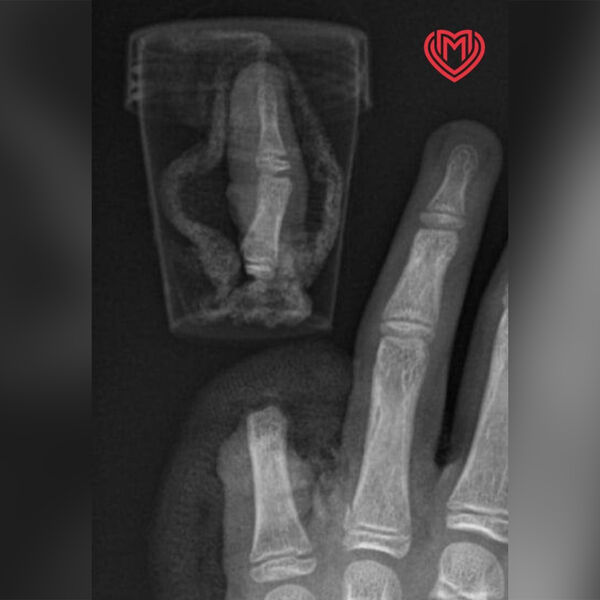

После этого мальчика экстренно госпитализировали в Филатовскую детскую больницу. Медики его осмотрели и приняли решение пришить ему палец на место.

В ходе операции хирурги соединили кости, сухожилия, а также сгибатели и разгибатели мизинца. Затем они сшили нервы и сосуды. Вмешательство прошло успешно и на данный момент ребенка выписали домой, однако он проходит программу реабилитации в больнице. Врачи дают ему благоприятный прогноз на восстановление функции мизинца.